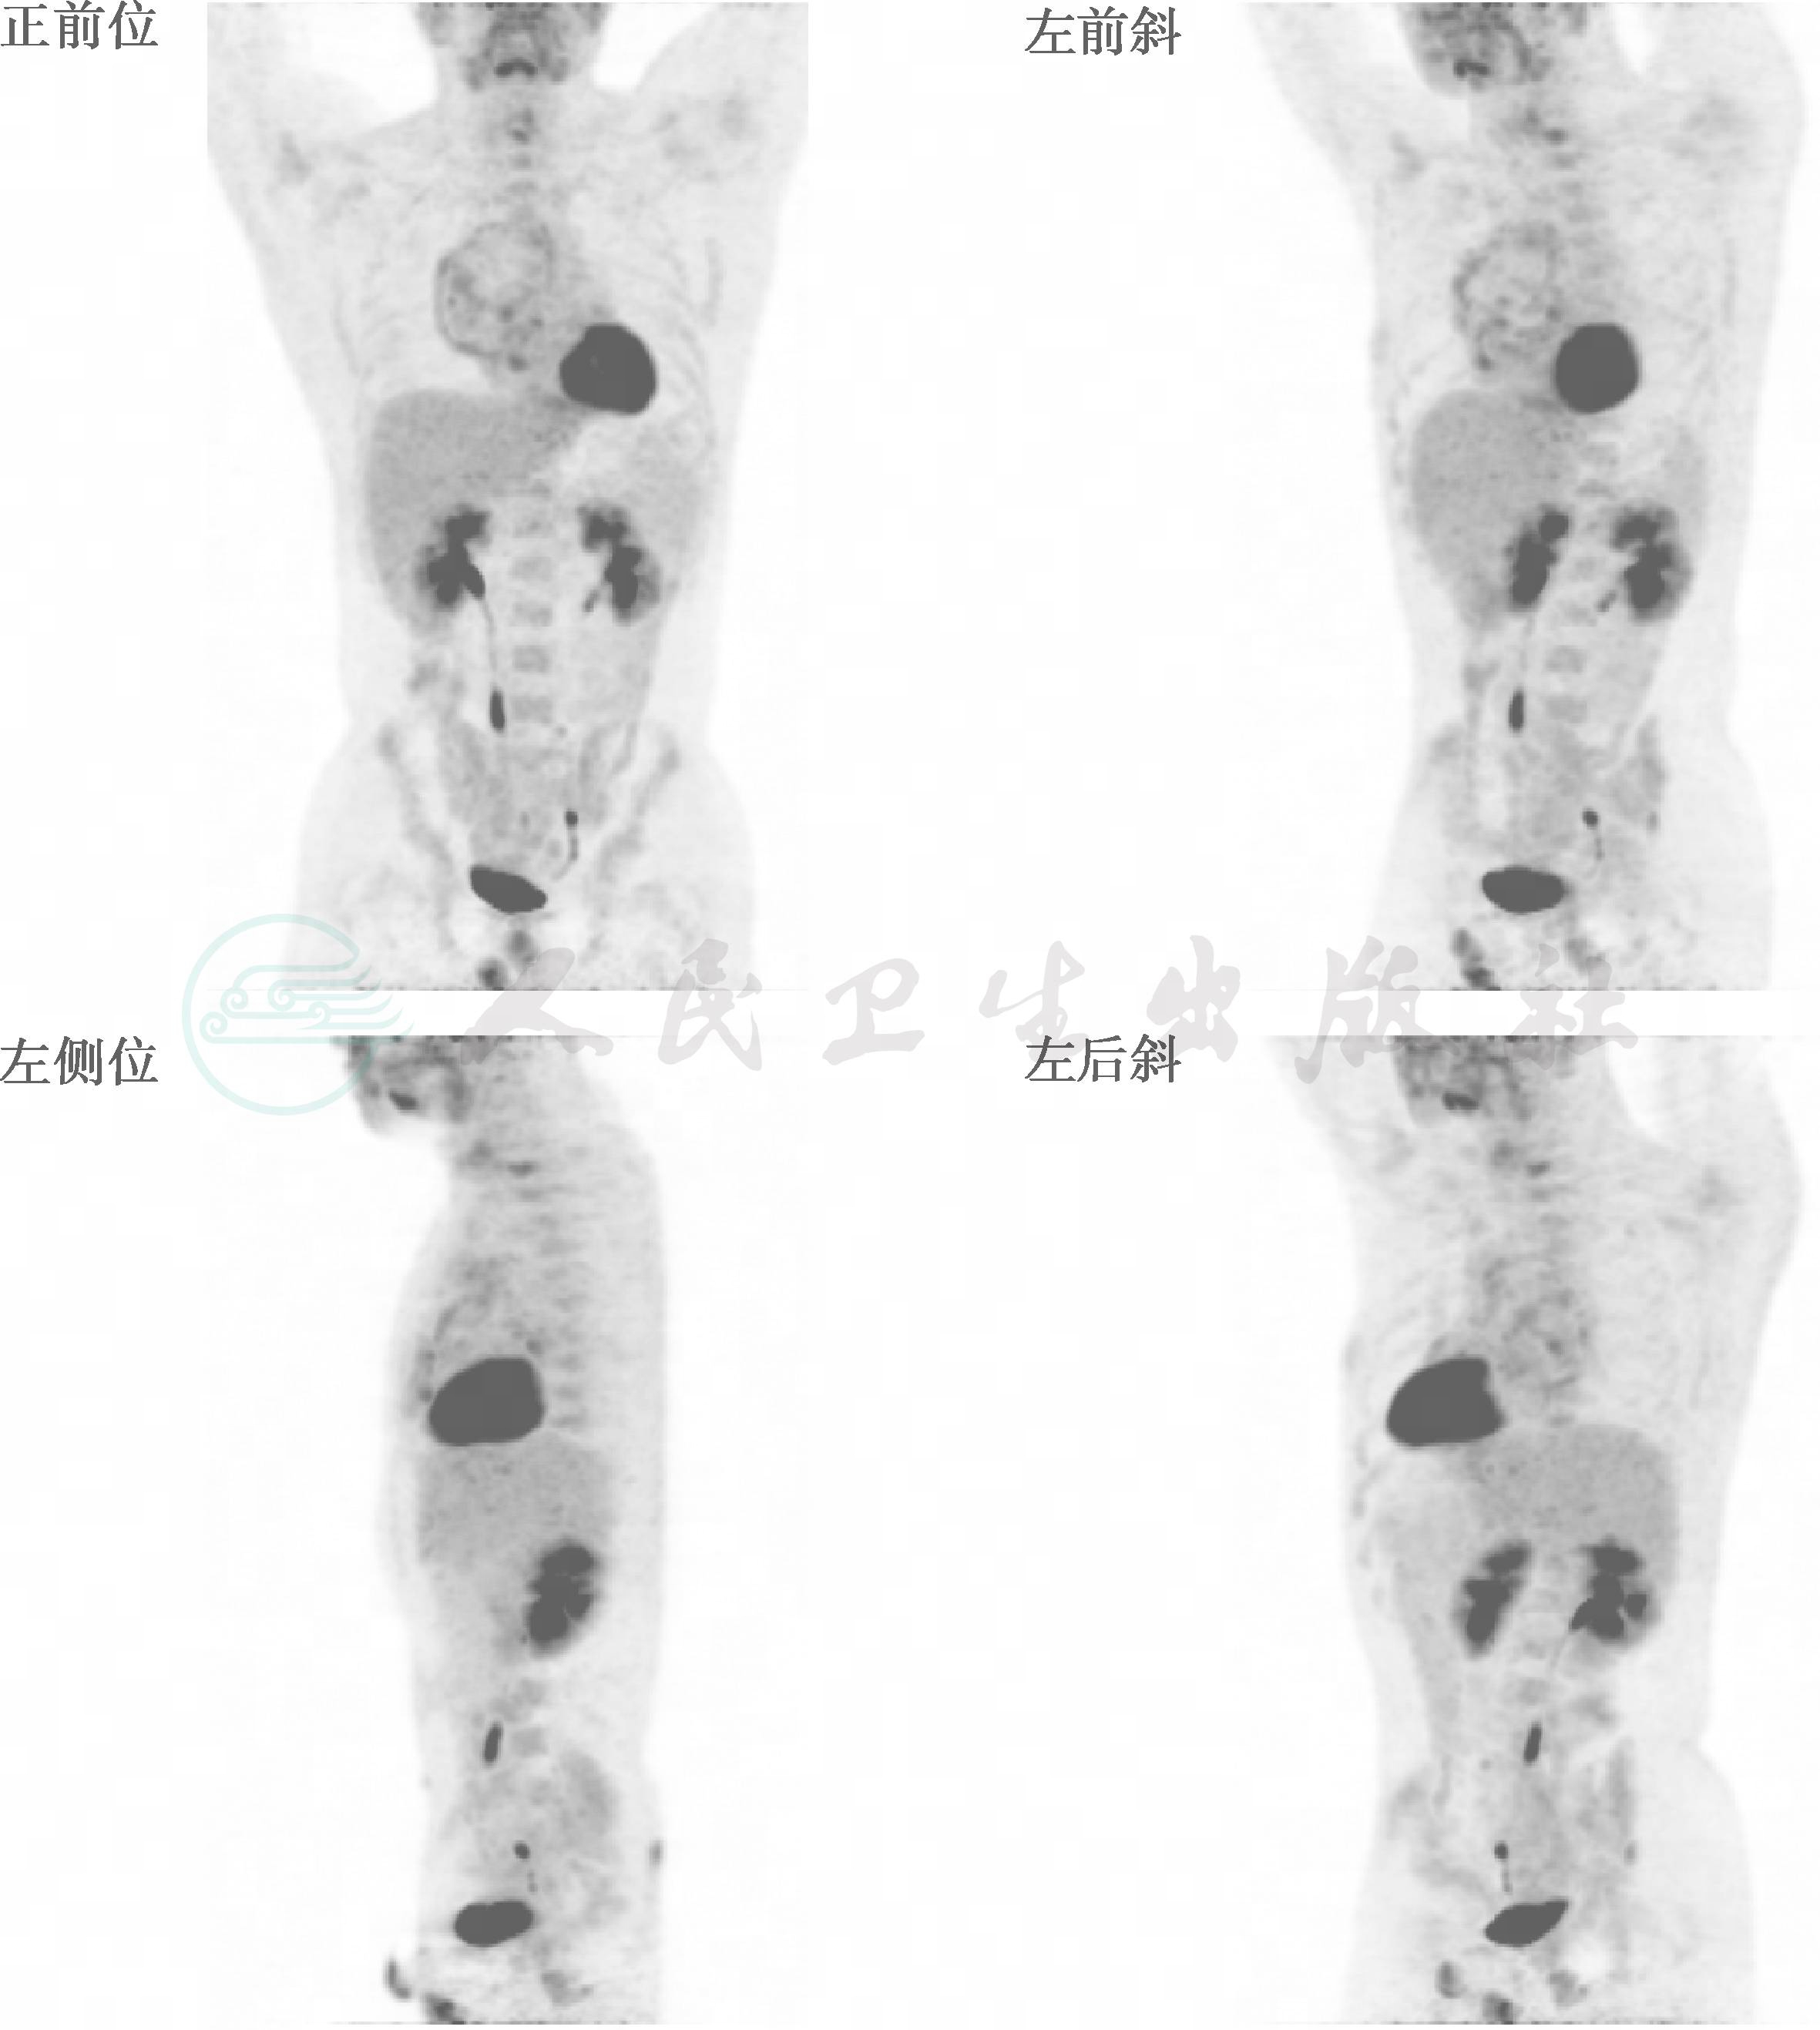

图1 FDG PET/CT 3D投影图

前纵隔巨大占位,中心放射性摄取减低,周边环形增高

前纵隔内可见一9.2cm×9.7cm×11.4cm占位,放射性摄取不均匀,周边呈放射性增高区,标准摄取值(SUV)1.3~3.1,中央呈放射性缺失区,CT值-3~53HU。双肺内多个类圆形结节影,大小0.9~1.4cm,放射性摄取轻度增高,SUV范围1.2~1.5。左肺下叶见斑片影,放射性摄取轻度增高。第7颈椎部分椎体呈放射性增高,大小为2.0cm×2.8cm×1.5cm,SUVavg约为3.1,最高为4.2。颈、胸、腹部及盆腔余部位未见明显异常。